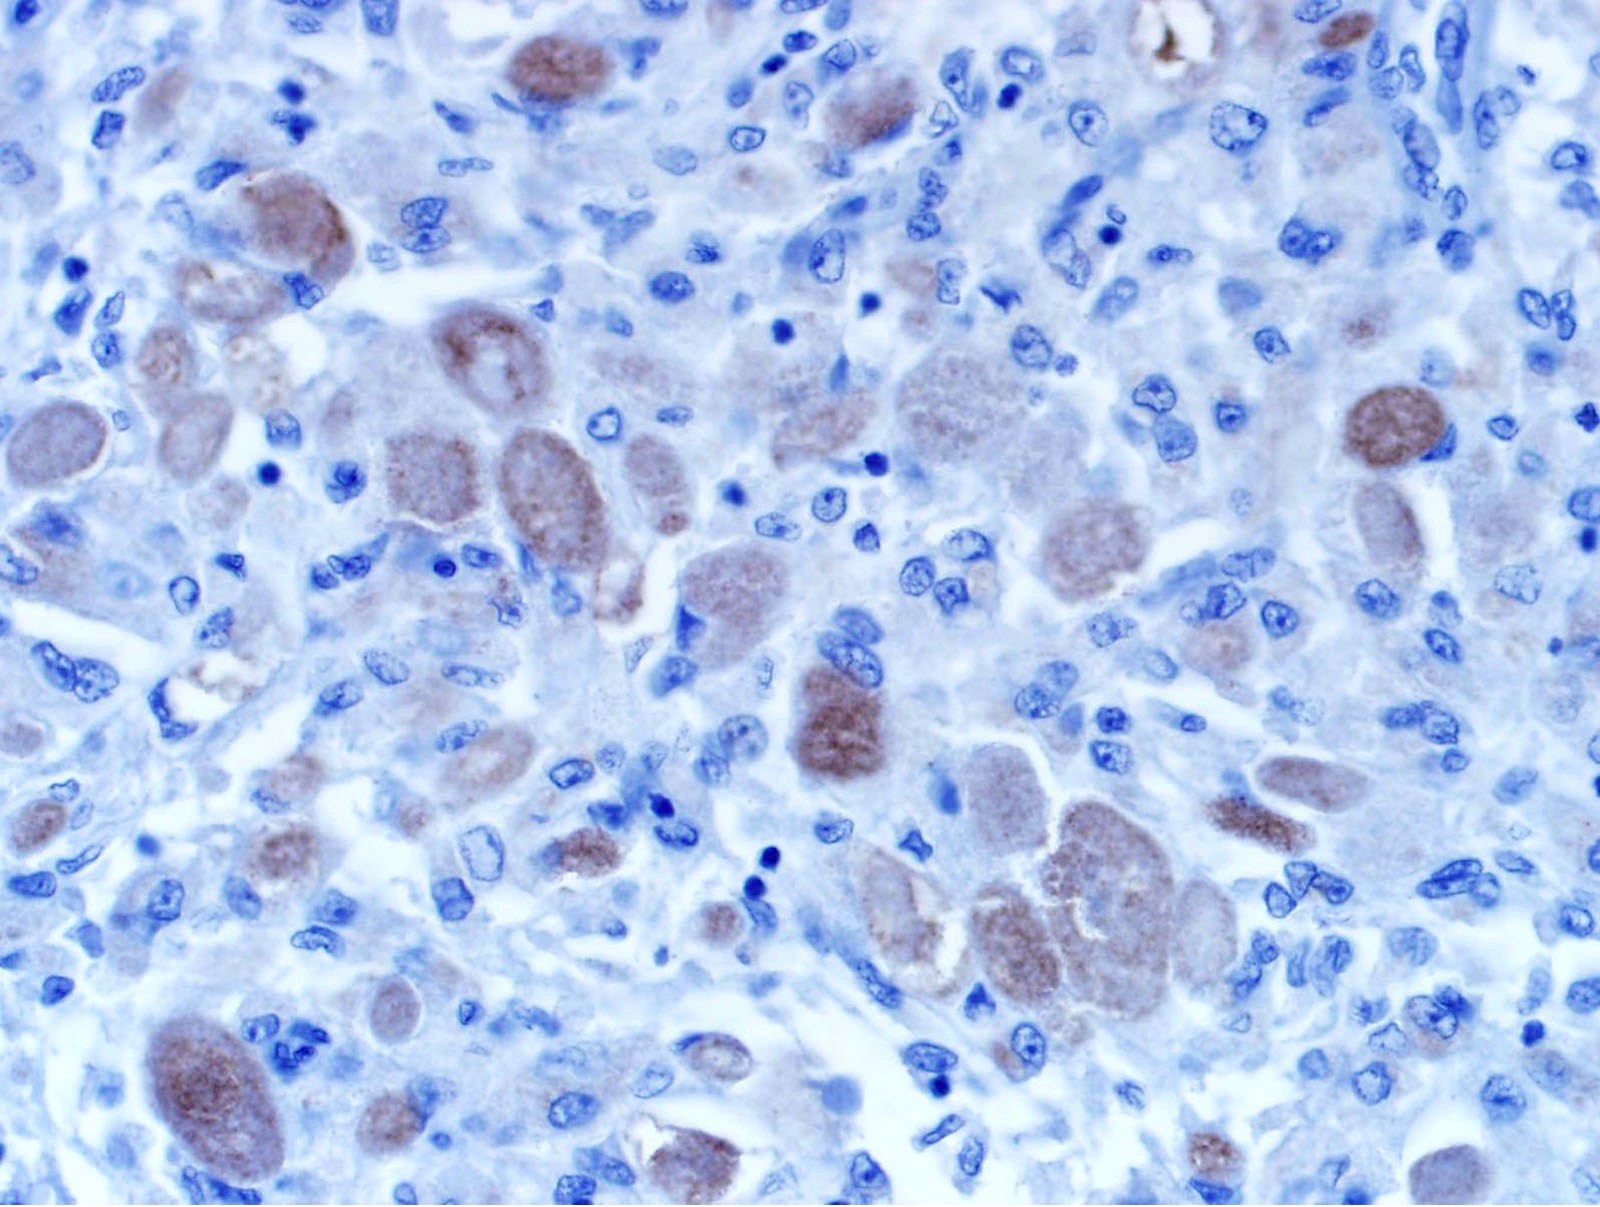

Microscopic (histologic) images

Contributed by Jarish Cohen, M.D., Ph.D.

Positive stains

- PASD, Sudan Black B, S100 (except for nonneural granular cell tumors), SOX10, NSE

- Variable staining for vimentin, CD68, NKI-C3 (CD63), MITF, CD56

- A subset of nonneural granular cell tumors express ALK

- References: Cancer 1982;49:1624, Histopathology 2012;61:997, Diagn Histopathol 1982;5:205, Cancer 1989;64:1455, Dermatology 1993;186:106, Am J Dermatopathol 2007;29:22, Hum Pathol 2015;46:813, Am J Surg Pathol 2018;42:1133